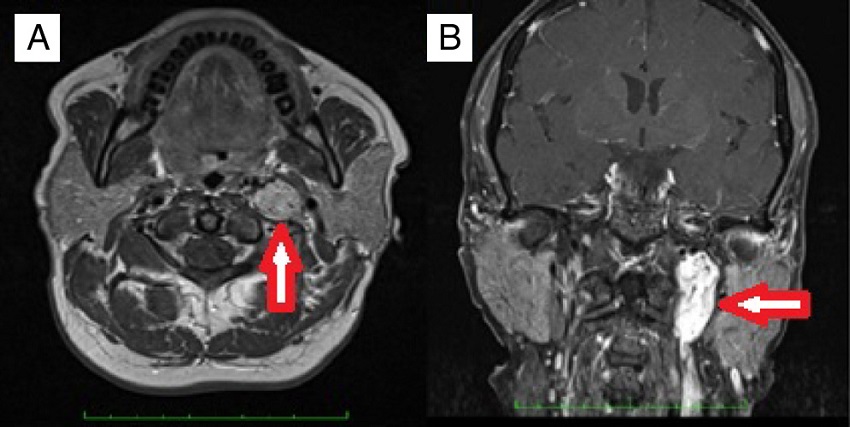

This study was conducted in the Otorhinolaryngology Department of Gazi University Faculty of Medicine. Approval was granted from the University Ethical Committee (12.01.2015 Decision Number: 16). The medical records of the patients undergoing operation with the diagnosis of temporal bone paragangliomas (TMPs and TJPs) between the years 2000 and 2015 were retrospectively reviewed. The patients who were only managed with SRT or wait-and-scan protocols were not enrolled in this study. The other exclusion criterion was lacking definitive histopathological diagnosis. A through otorhinolaryngologic examination was performed. The House-Brackmann (HB) grading system was used to determine facial nerve function.12 A magnetic resonance imaging (MRI) was routinely performed before the operation (Fig. 1). Fisch classification13,14 was used for staging tumors. Digital Subtraction Angiography (DSA) was performed for differential diagnosis or preoperative embolization. PVA (polyvinyl alcohol) particles were used for embolization. Blood and urine catecholamine levels were not routinely studied. Audiometric examination was performed with pure tune audiometry. All the operations were performed under general anesthesia. Erythrocyte suspension (ES) was prepared before the operation. Simple or modified radical mastoidectomy (MRM) and tympanoplasty after a post-auricular incision was performed for TMPs whereas infratemporal fossa type A (ITFA-A) procedure was used for TJPs (Fig. 2). In the follow-up all of the patients underwent MRI to exclude any tumor recurrence or to follow residual tumor size if exists. Demographic characteristics, presenting symptoms and signs, radiologic findings, operative techniques, complications and follow up data were all reviewed in detail.

The main treatment modalities for TBPs are surgery and radiotherapy. Total tumor resection without major complications like cranial nerve deficit is the main goal of the operation. Canal wall up or down tympnomastoidectomy with or without facial recess approach is commonly adequate for the removal of TMPs.6 However IFTA-A is frequently needed for the total removal of TJPs, especially in case of intracranial extension. As defined by Fisch in 1982 it includes a cervical extension of a post-auicular incision to maintain best neurovascular control by exposing jugular bulb, jugular vein and carotid artery following mastoidectomy, facial rerouting, cervical incision and blind closure of the ear canal.13,14 Salt and pepper appearance meaning areas of high and low intensity on MRI is typical for PGs.23 Nevertheless DSA may be performed to confirm the diagnosis in case of suspicion.23 In surgical candidates DSA may be performed just prior to the operation for selective embolization. Ascending pharyngeal artery and its branches are known to be the main feeding vessel for TBPs.23 However in the present study in the order of incidence occipital artery, posterior auricular artery and ascending pharyngeal artery were found to be most common afferent vessels. In four cases with TMPs there was not any afferent vessel identified with DSA. Preoperative embolization is not advised for Fisch class A tumors while it is strongly recommended for Fisch class C and D tumors. The main objective of preoperative embolization is to reduce vascularity and thus bleeding during surgery. In the retrospective study of Murphy et al., intraoperative bleeding, operation time and hospital stay for TJPs, were shown to be significantly reduced after preoperative embolization.24 However preoperative embolization for TBPs may also cause permanent cranial nerve palsy.25